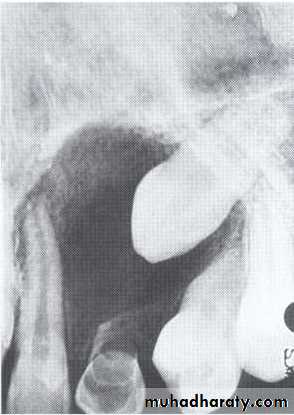

• It is located between the maxillary central incisors (which are vital). This lesion dose not exist as an entity but it represents an incisive canal cyst.• Nasopalatine Cyst

Also called nasopalatine canal cyst, incisive canal cyst,median palatine cyst,or median anterior maxillary cyst.*It is located in the midline between the upper central incisors. Note the superimposed shadow of nasal

spine causing the cyst to appear heart shaped.

The teeth are vital.

This cyst causes the roots of the central incisors to

diverge, and occasionally root resorption occur.

*Treatment by excision.